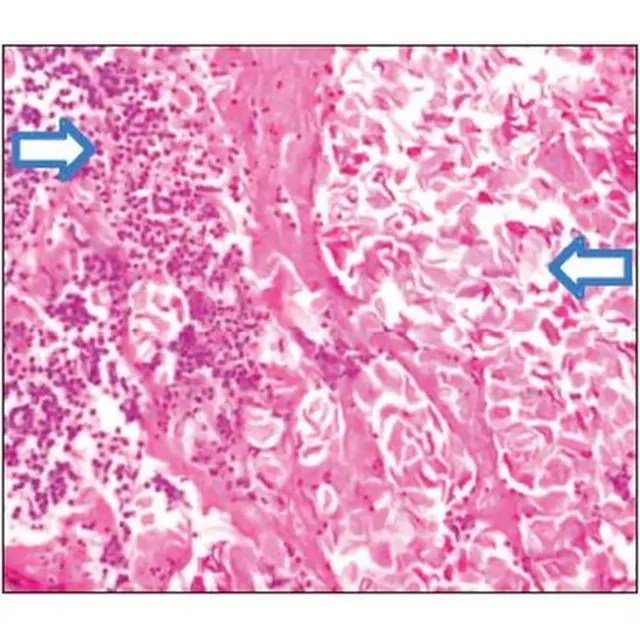

Были у этого случая и необычные клинические явления: присутствие патогенов (микроорганизмов), которые обычно не обнаруживаются при ушных заболеваниях, а также необъяснимых ранок.

Мысль об этом возникла во время первой биопсии, когда врачи заметили, что ребенок, попав в больницу, сразу стал поправляться, вспоминает хирург.